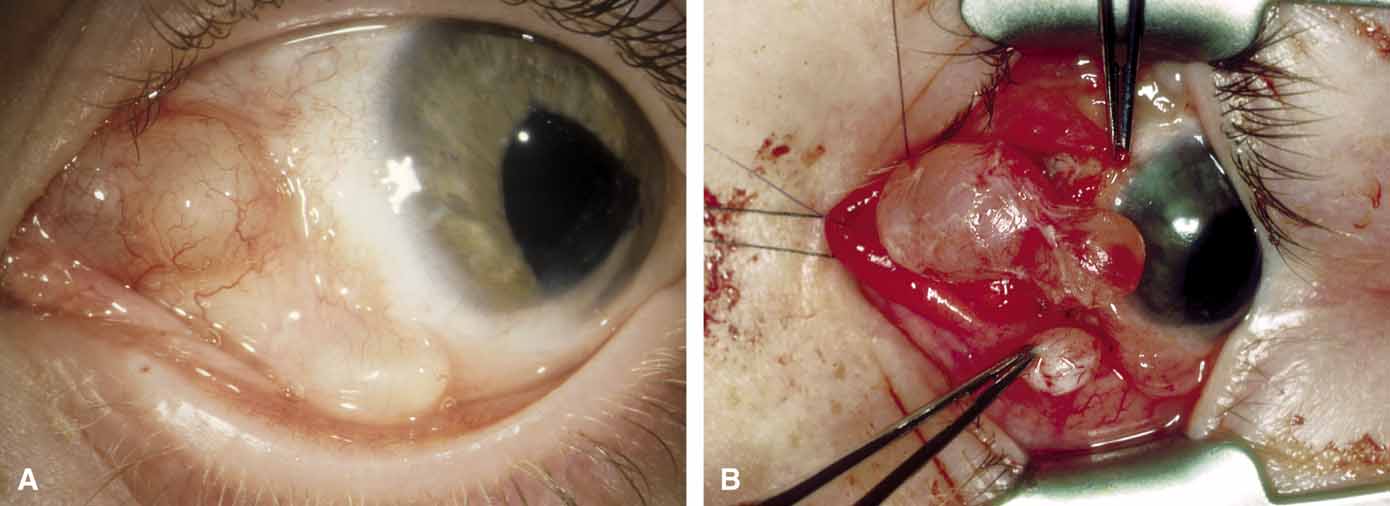

It is often cosmetic considerations that prompt the parents of an affected child to seek treatment. These cysts enlarge as the child grows and the possibility of accidental traumatic rupture is ever present. In adults, mass effect or periorbital inflammation due to leakage of cyst contents may prompt medical attention and surgical removal (Fig. 4).5,10

Surgical removal is the treatment of choice. The surgical approach is dictated by the location of the cyst and its association with boney suture lines. In the majority of juxtasutural dermoid cysts, the lesion can be reached through an incision placed directly over it. Because many of these cysts are located along the superior orbital rim, a brow incision may be placed directly over the cyst along the superior orbital rim. Because of a potentially visible scar, however, use of an upper eyelid crease incision has been advocated.11 A posteriorly located cyst (soft-tissue dermoid) or a bilobed cyst with transmission through the orbital rim (sutural dermoid), in contrast, requires more careful planning for an approach through an anterior and/or a lateral orbital route. Large intradiploic cysts and cysts located along the orbital roof and temporal fossa may require multidisciplines and approach transcranially or a temporal skull base approach.12,13

Surgical extirpation should be complete. Intraoperative rupture of the cyst with release of its contents into the orbit may incite a mild but smoldering granulomatous inflammation. The contents of these cysts may vary from an oily, tan liquid to a cheesy, yellow-white material. When inadvertent rupture occurs, the operating surgeon must flood the wound with irrigating solution to be sure that all this material has been washed away. Complete removal of the cyst wall is curative; incomplete removal may be followed by recurrence. Although marsupialization of deep and extensive dermoid cysts has been advocated by some practitioners,14 this technique is not recommended.8